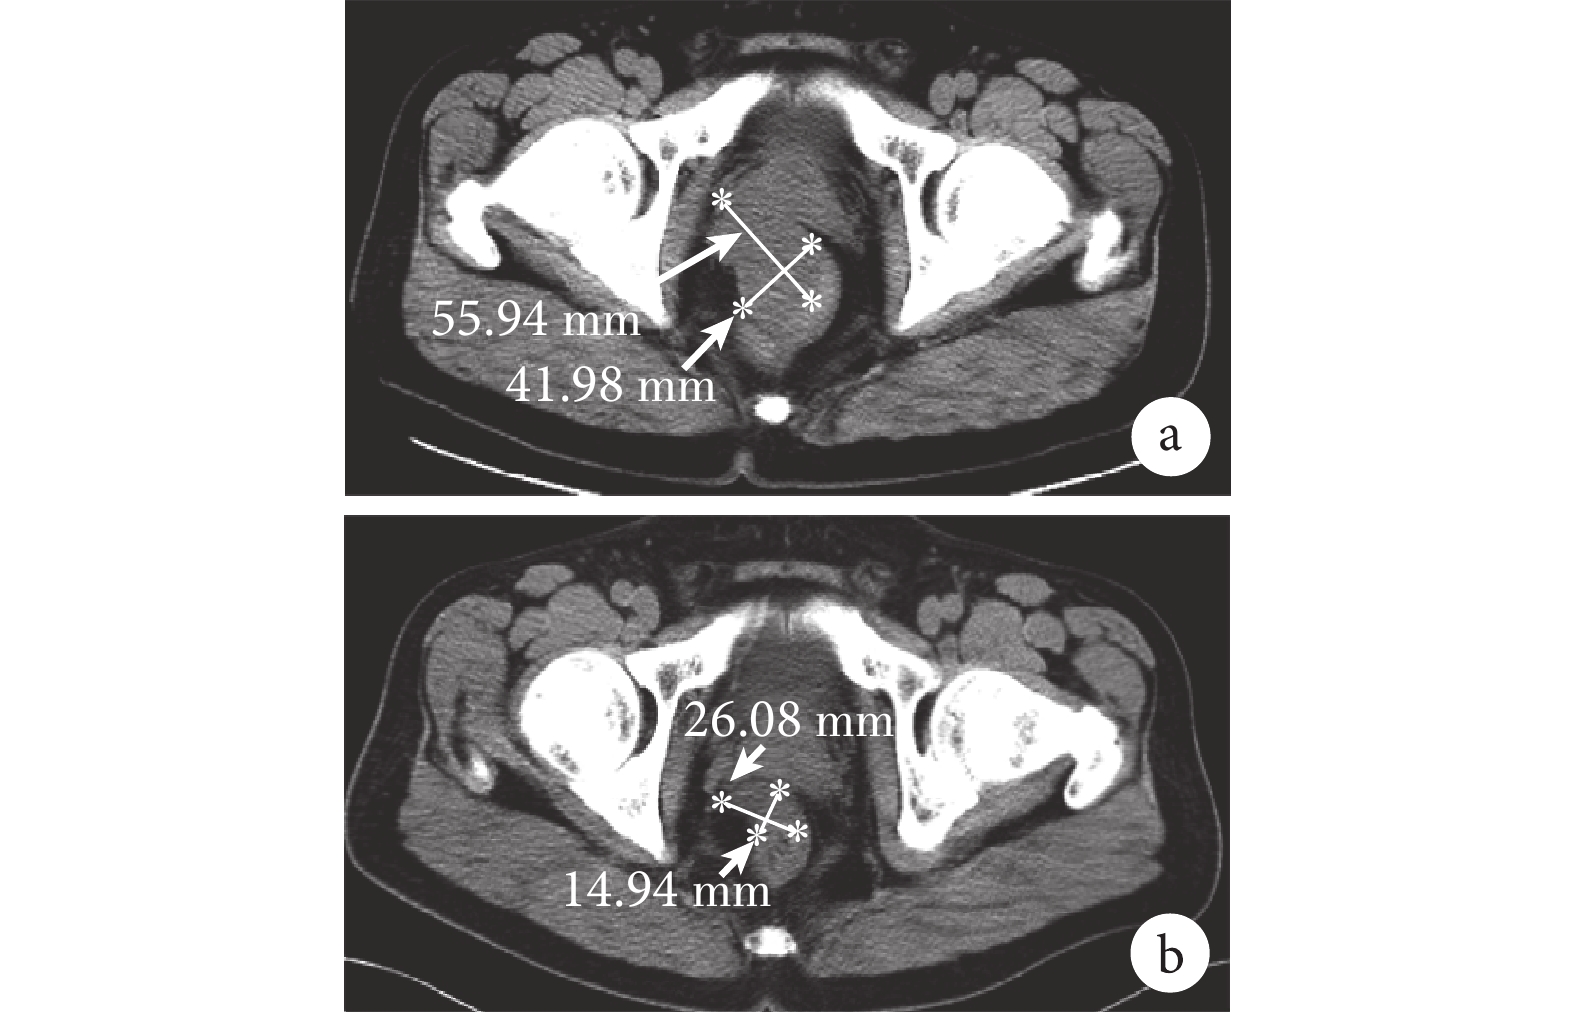

本組 3 例經術前活檢確診者,接受了 IM 新輔助治療(400 mg/d),4 個月后腫塊明顯減小(圖 4),再行手術完整切除腫瘤。29 例手術患者的手術時間為 34~205 min、(94.2±4.7)min;術中出血量為 10~60 mL、(30.9±1.3)mL;術后住院時間為 5~23 d、(11.7±4.4)d。術后 7 d 發生吻合口漏 1 例,予以禁食、補液、引流管沖洗等處理,愈合良好;術后 1 d 發生切口滲血 2 例(局部切除患者),予以紗布卷肛門填塞止血后滲血停止。

直腸間質瘤在結腸鏡下均表現為扁平黏膜隆起,表面光滑,形態尚規則,基底部寬(圖 1)。本組 29 例患者行 CT 或 MRI 檢查,表現為盆腔邊界清楚的軟組織腫塊,主要為黏膜下、肌間層或漿膜下的圓形或分葉狀腫塊,其向腸腔內、外突出生長,直腸可呈不同程度地受壓和變窄,腫瘤密度及信號不均,可見壞死、鈣化和出血;增強掃描時腫瘤邊緣帶可呈中等程度結節樣強化,腫塊中心部分無強化,呈壞死樣改變(圖 2)。

影像學輔助檢查具有相對特征性,利于對直腸間質瘤作出初步診斷。有研究[8]報道,直腸間質瘤典型的 CT 和 MRI 表現為:黏膜下、肌間層或漿膜下的圓形或分葉狀腫塊,邊界清晰,腫塊主要向直腸腔外生長,直腸可呈不同程度地受壓和變窄。CT 增強掃描時腫瘤邊緣帶呈中等程度結節樣強化,腫塊中心部分無強化,呈壞死樣改變;MRI 表現為動脈早期病灶周邊顯著不均勻強化,而中心區無明顯強化[9]。因此,影像學檢查可以協助判斷腫瘤進展的狀況,提高術前診斷的準確性,為手術方案的制定提供指導依據[10]。本組 29 例行 CT 或 MRI 檢查者所表現的影像學特征與文獻[8-9]所述基本相符。